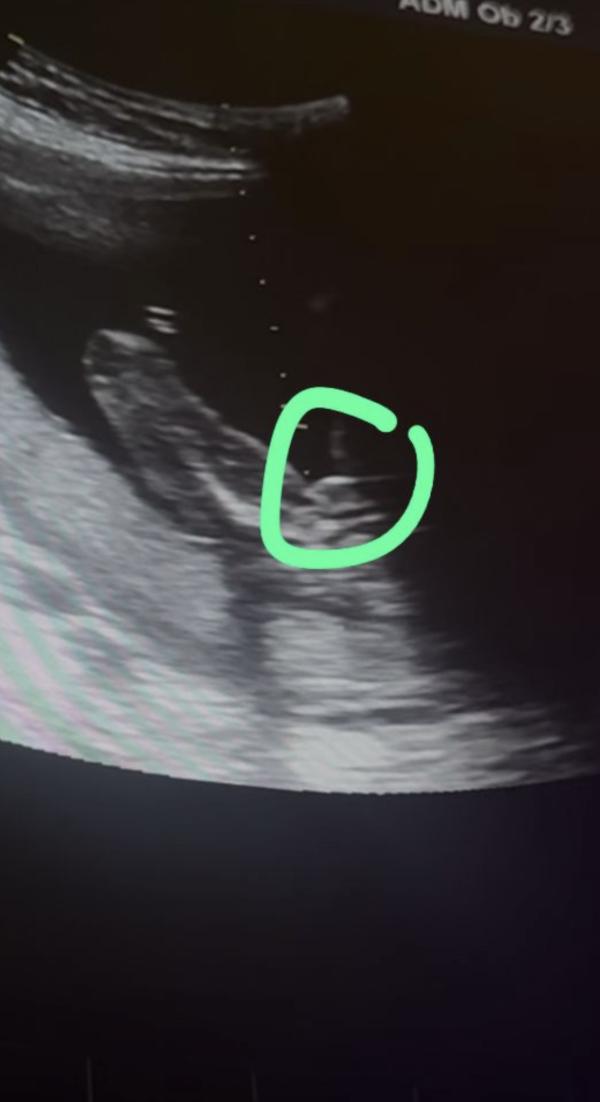

Определение пола ребенка по УЗИ: девочка или мальчик?

Это точно девочка же да ? 😂🥹

На 2 скрининге все таки подтвердили что будет девочка, не опять, а снова 😂😆